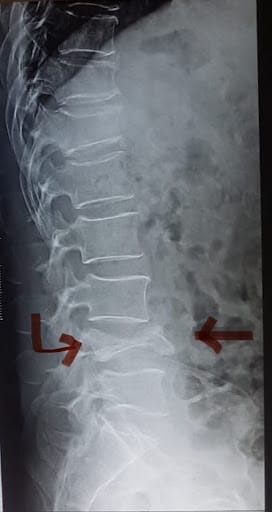

These are relatively common fractures in elderly individuals as the spine is one of the first bones to lose bone density and the mechanics of the spine is such that the lack of bone strength can often result in spine fractures even with little to no injuries to the spine. Hence, even the simplest of manoeuvres to a weak spine such as bending forward to pick up weight (without an actual history of falls or trauma to the body) can leave the spine most vulnerable to osteoporotic stress fractures. Similarly, in the case of falls/ injuries, the loading weight on the spine in addition to the force of injury that the individual's spine is susceptible to can result in compression fractures.

Cause of injuries:

• Injuries to the spine such as fall in a sitting position, or high-velocity injuries such as road traffic accidents and fall from height injuries.

• In the cases of severely weakened bones. Bending forward for prolonged periods when the spinal bone (vertebra is too weak to handle such a manoeuvre)

Preferred treatment option:

The type of treatment mainly depends on factors such as:

• Spine fractures that also cause an injury to the spinal cord, which is enclosed within the vertebra, vary in severity, ranging from simple fractures to multiple fragment fractures.

• The threat of the current fracture to injure the enclosed spinal cord.

• Risk of spinal deformity if the fracture is untreated or inadequately treated.

Depending on these factors:

Non-operative management for simple wedge compression fractures which have retained significant height even after the compression and do not pose a threat to the spinal cord or risk of progressive spinal deformity.

In case of stable spine fractures which pose no threat to the spinal cord but cause severe prolonged pain of the back, an alternative minimally invasive option of treatment involves a day care procedure known as Vertebroplasty or kyphoplasty under local Anaesthesia.

Surgical spinal stabilisation using rods and screws are reserved for “burst” fractures which are unstable, pose a risk of spinal cord injuries (or have already resulted in a spinal cord injury) or the the fractured vertebrae is too severely crushed to achieve any adequate restoration of the height of the vertebral body via minimally invasive procedures such as Vertebroplasty/ kyphoplasty.

Recovery Period:

In spine fractures where conservative or non operative modality of management is pursued, the individual will require a minimum of 4 weeks of STRICT bed rest following which the patient is then reassessed and started on walking exercises and other spinal rehabilitation activities.

In individuals who have undergone minimally invasive treatment (Vertebroplasty or kyphoplasty) the patient is mobilized immediately after the procedure (pain-free) and is allowed to walk with no restrictions. The patient is then allowed to resume all his/ her routine activities within 5 to 7 days.

In individuals upon whom spinal stabilization surgery is performed, the individual is allowed to get out of bed and start walking within 24 hours and can resume all activities within 2 weeks.